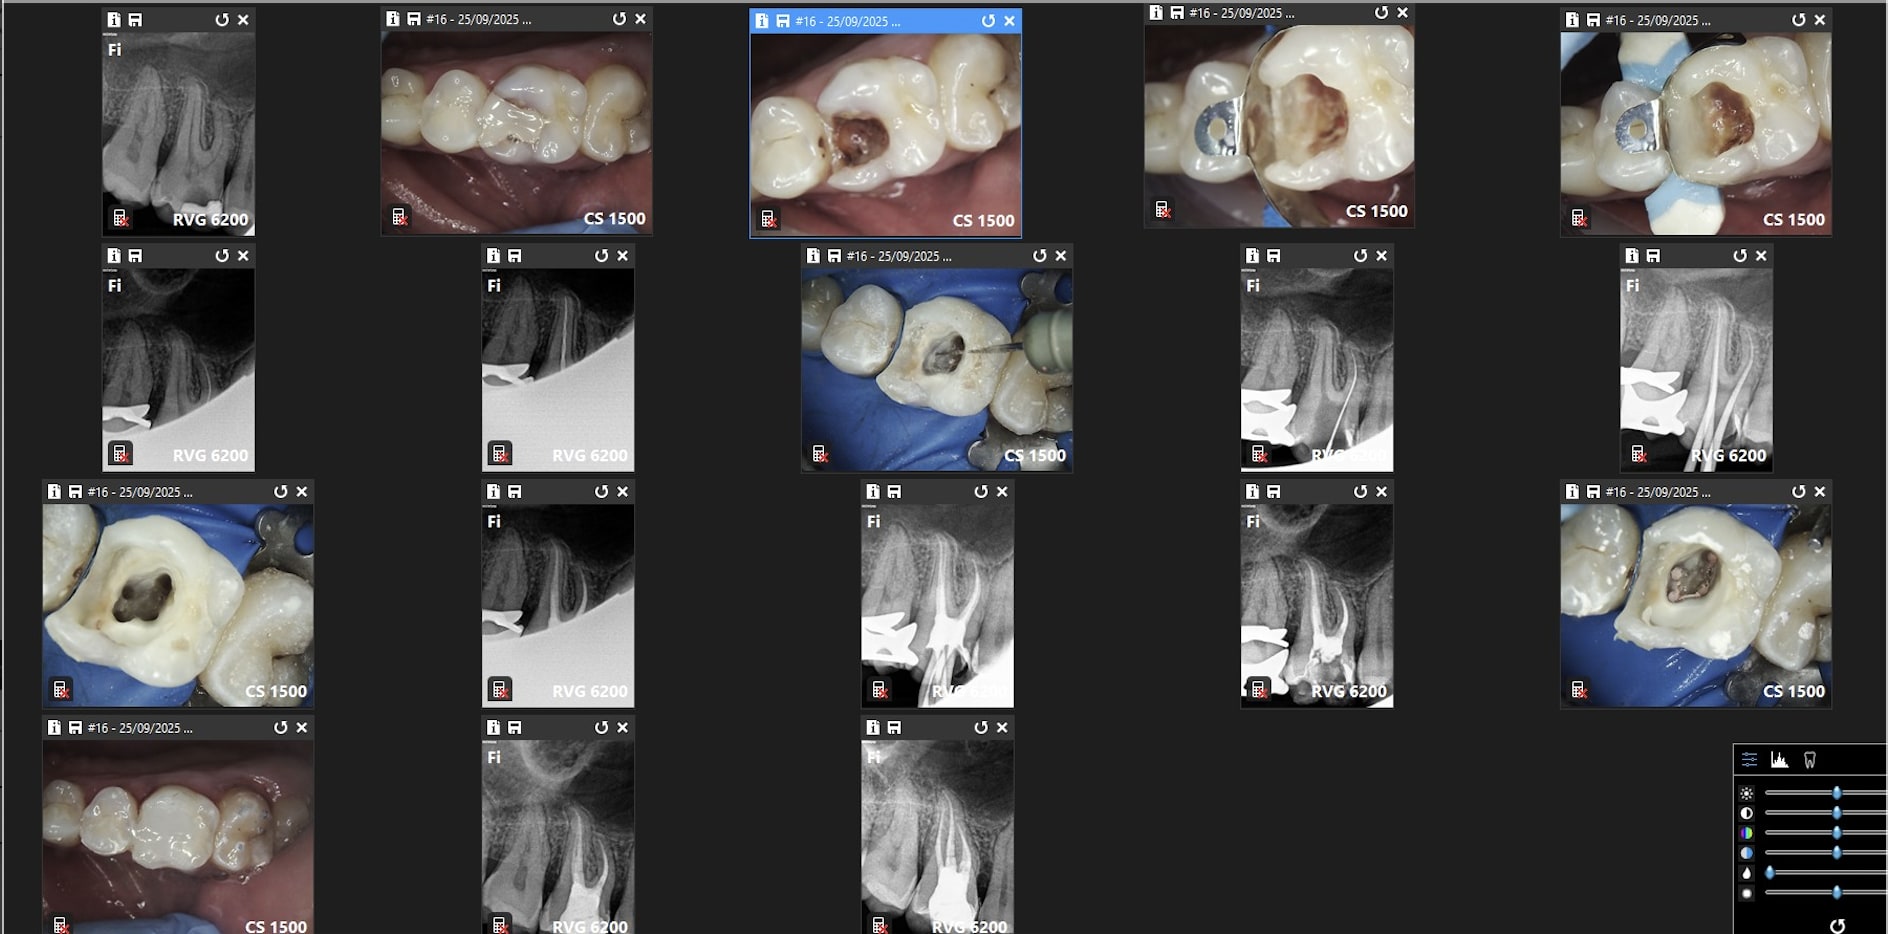

Comparaison des traitements de 2 praticiens différents au même tarif. Même patient 16 26. Pourquoi se faire chier aucun souci sur 26. ,

> Comparaison des traitements de 2 praticiens différents au même tarif. Même

> patient 16 26. Pourquoi se faire chier aucun souci sur 26. ,

neanmoins la question de gabzou concernant le % de cas réellement difficiles est intéressante car chicot tu illustres ce propos par des cas que tu dois trouver emblématiques datant de 2019/2020

j'ai pris au pif. sinon plus récent. je ne les capture pas toutes.

Indépendamment du reste, il y a clairement une racine MV non traitée dont on distingue le canal, ce qui est l'anatomie standard d'une 26.

Conclusion, le praticien l'a sciemment ignorée pour aller plus vite.

On peut discuter de la rémunération, des raisons qui ont amené ce praticien à choisir de bâcler le travail, mais il est indiscutable que le praticien ne peut pas avoir ignoré avoir fait n'importe quoi.

J'ai bien précisé que tout n'est pas facile. Cette 26 l'est, je n'ai quasiment aucun doute.